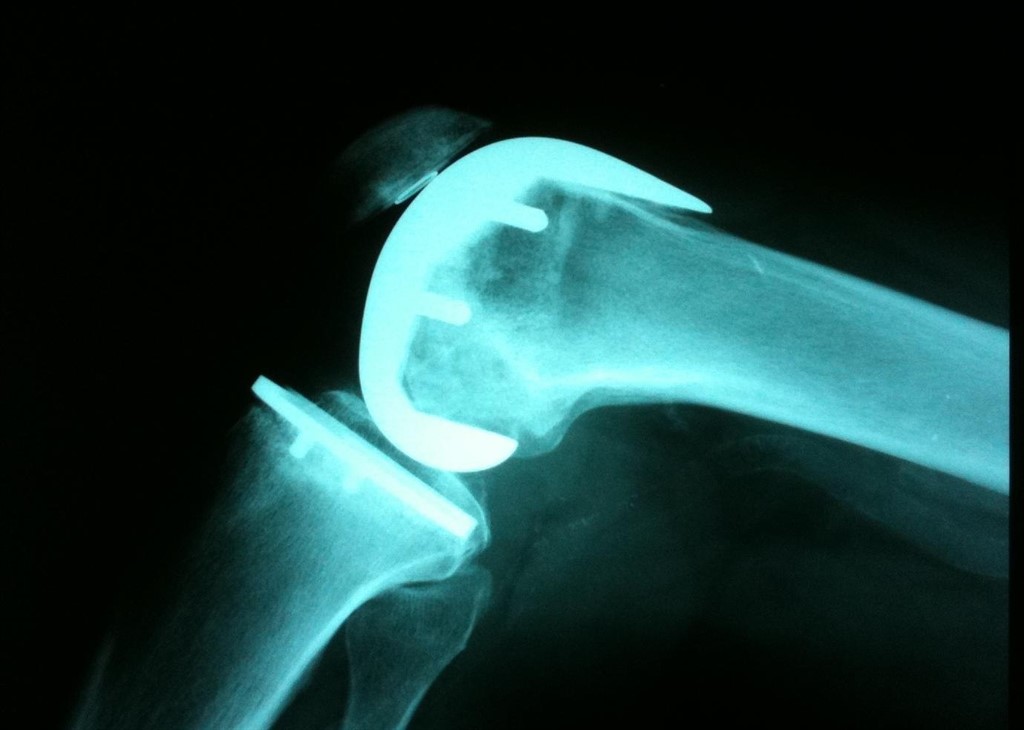

Pierna Hinchada Después De Operación De Prótesis De Rodilla, , , , , , , 0, Rodilla hinchada tras una prótesis: ¿es normal?, jlfisios.com, 800 x 510, jpeg, WebSi, la hinchazón y el dolor después de una prótesis total o unicompartimental de rodilla son fenómenos comunes. Puede durar varias semanas o. WebPara una correcta recuperación después de una prótesis de rodilla se necesita cumplir un estricto programa de rehabilitación física. Acompañado de tu fisioterapeuta,. WebUna podría ser, si será el momento adecuado, pero en realidad no existe nada que nos pueda indicar con precisión cuándo debe realizarse el reemplazo de rodilla., 20, pierna-hinchada-despues-de-operacion-de-protesis-de-rodilla, Novedades y Muebles WebSi, la hinchazón y el dolor después de una prótesis total o unicompartimental de rodilla son fenómenos comunes. Puede durar varias semanas o. WebPara una correcta recuperación después de una prótesis de rodilla se necesita cumplir un estricto programa de rehabilitación física. Acompañado de tu fisioterapeuta,. WebUna podría ser, si será el momento adecuado, pero en realidad no existe nada que nos pueda indicar con precisión cuándo debe realizarse el reemplazo de rodilla.

WebSi existe inflamación el pierna o la rodilla, lo cual suele ser bastante frecuente y normal después de haber estado en el quirófano, es aconsejable que se mantenga siempre en. WebPorque Se Inflama La Pierna Después De Operación De Cadera Las complicaciones tras la operación deprótesis de cadera son poco comunes, aunque conviene conocerlos de. WebEl dolor en extensión de la prótesis de rodilla suele referirse a la zona posterior de la rodilla, sugiere contractura de los isquiotibiales. Suele agravarse si realizamos la. WebCon la pierna sana flexionada, apoyando la planta del pie en la cama (esto es para que no sufra la espalda al realizar el ejercicio), elevaremos la pierna operada. Web¿Tienes la rodilla hinchada después de una cirugía de prótesis de rodilla? Algunas personas después de la cirugía presentan la rodilla hinchada, hematomas y dolor al. Web¿Tienes la rodilla hinchada después de una cirugía de prótesis de rodilla? Algunas personas después de la cirugía presentan la rodilla hinchada, hematomas y. WebGRAN HEMATOMA TRAS CIRUGÍA DE RODILLA. Una de las consecuencias habituales de la cirugía artroscópica de rodilla para el implante de plastia. WebLa incisión se hace por la parte delantera de la rodilla, con una longitud de unos 25 centímetros aproximadamente. Cuando pases a la reanimación, ya te habrán puesto.

WebTras implante de prótesis de rodilla sufro hinchazón, dolor agudo y al tocar la zona está caliente. Tras biopsia del líquido sinovial el resultado es el siguiente: "fibrosis y proceso. Web10 dias después de una prótesis total de rodilla,sufre mucho dolor al movilizar, sobre todo no es capaz de flexionar, pierna y pie muy hinchado y con muchos. WebEste aumento de aporte de sangre lleva consigo una serie de síntomas: hinchazón, enrojecimiento y calor en la rodilla. A pesar de que el enrojecimiento y el.

WebGRAN HEMATOMA TRAS CIRUGÍA DE RODILLA. Una de las consecuencias habituales de la cirugía artroscópica de rodilla para el implante de plastia. WebLa incisión se hace por la parte delantera de la rodilla, con una longitud de unos 25 centímetros aproximadamente. Cuando pases a la reanimación, ya te habrán puesto. WebDescripción general. Una rodilla se hincha cuando se acumula exceso de líquido en la articulación de la rodilla o a su alrededor. Los proveedores de atención.